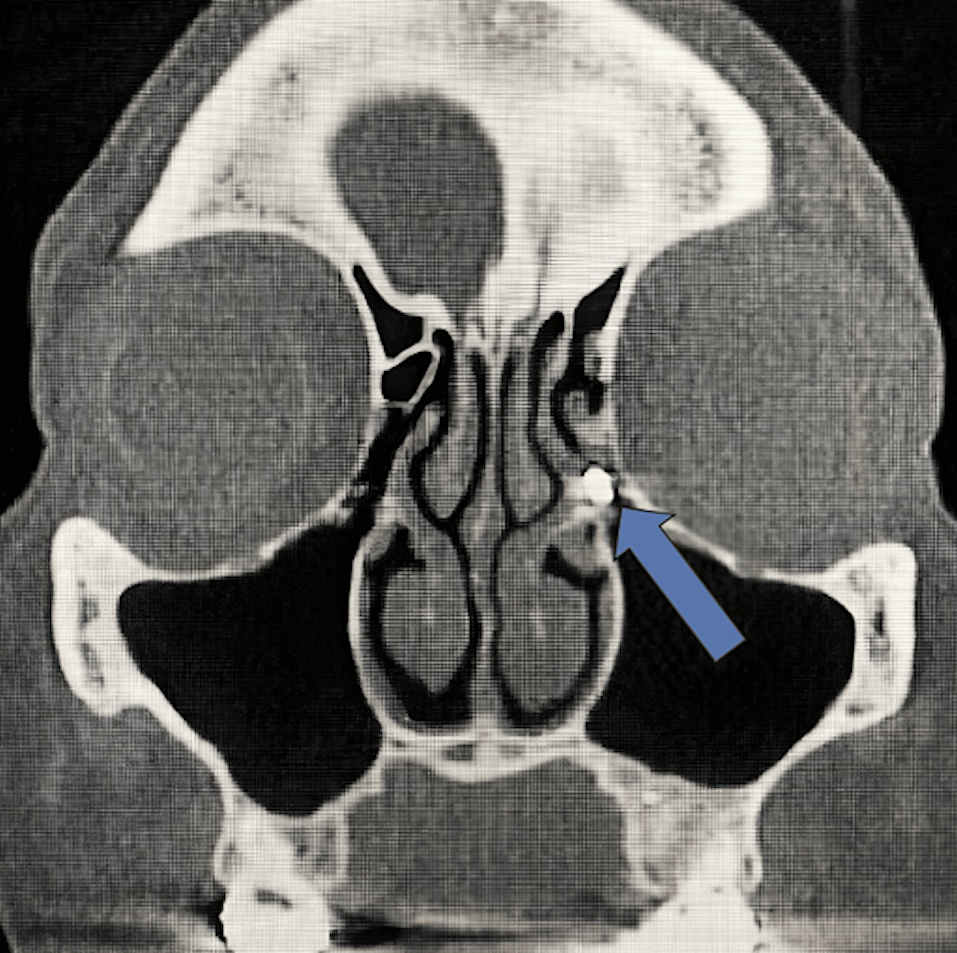

Later, a radiologist interpreted her CBCT, noting that tooth #31 had a normal periapical appearance. However, the woman's "adjacent lingual cortical bone had a lytic and erosive appearance" that stretched about 16 mm in anteroposterior dimension by 7 mm craniocaudally that was limited to the thickness of the lingual cortex.

Five days later, the patient returned to the original endodontist, complaining of sensitivity, as well as tenderness and pressure when biting. There was no swelling, but tooth #30 was "responsive but lingering to cold testing." The original endodontist review of the CBCT, as well as that of the radiologist, revealed a hyperdensity near the tip of tooth #30 with an untreated root, distobuccal tooth #31, the authors wrote.

The endodontist diagnosed the woman with an iatrogenic injury from the rubber dam clamp, not osteomyelitis. Furthermore, CBCT images revealed a concave outline of missing lingual cortical bone that matched the contour of the stainless-steel clamp. A root canal was performed on tooth #30 and the untreated root of tooth #31, the authors wrote.